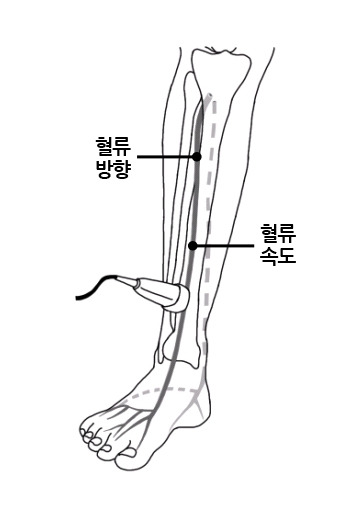

3) 탐촉자로 혈관 확인

- 초음파 기계의 탐촉자를 피부 위에 대고

- 혈관을 따라 천천히 이동

이때 검사자는

- 혈관 두께

- 혈관 내강

- 혈류 속도

- 혈류 방향

을 동시에 본다.